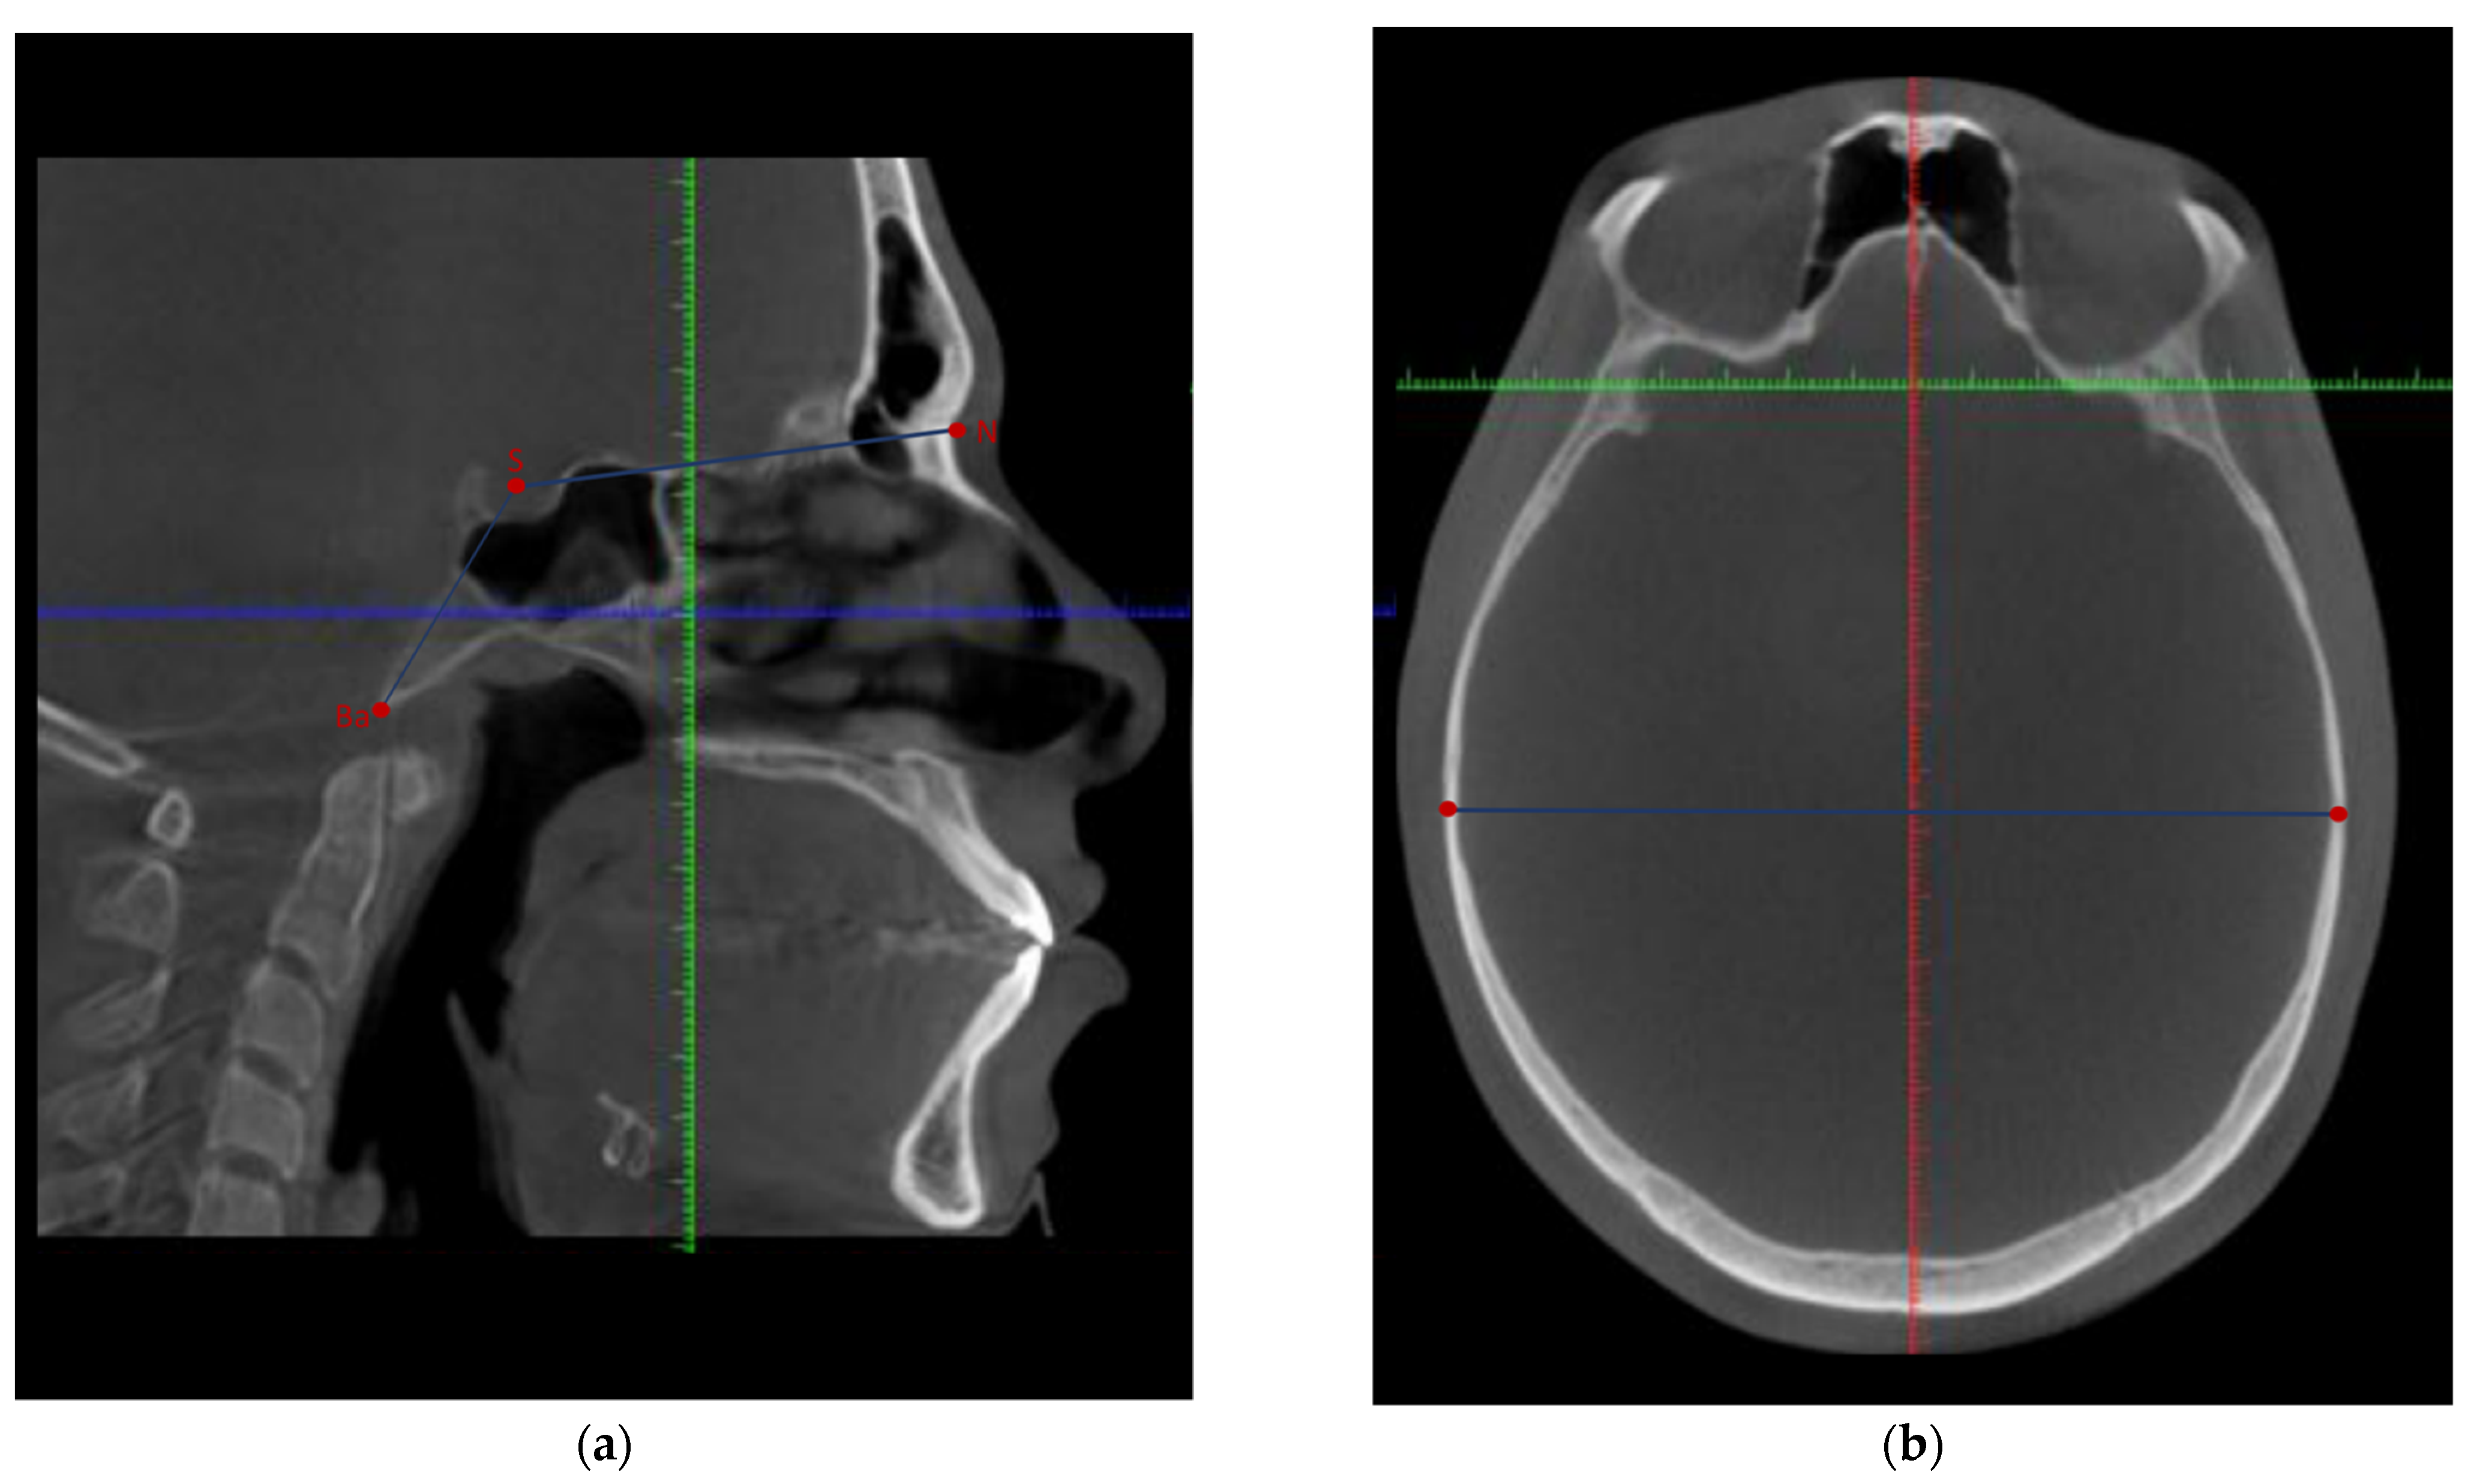

| Landmark | Abbreviation (Unit) | Definition | Sagittal View | Axial View | Coronal View |

|---|---|---|---|---|---|

| Sella-Nasion | S-N (mm) | Anterior cranial base length in millimeters | Distance between the middle point of the pituitary fossa and the anterior-most point of the frontonasal suture | Distance between the middle point of the anteroposterior and lateral width of the pituitary fossa and the middle–anterior-most point of the frontonasal suture | Distance between the middle point of the lateral width of the pituitary fossa is determined by the sagittal and axial views and the anterior–middle point of the frontonasal suture |

| Sella-Basion | S-Ba (mm) | Posterior cranial base length in millimeters | Distance between the middle point of the pituitary fossa and the inferior–posterior-most part on the anterior margin of the foramen magnum | Distance between the middle point of the anteroposterior and lateral width of the pituitary fossa and the anterior-most point of the anterior margin of the foramen magnum | Distance between the middle point of the lateral width of the pituitary fossa determined by the sagittal and axial views and the middle point on the anterior margin of the foramen magnum |

| Nasion-Basion | N-Ba (mm) | Total cranial base length in millimeters | The total linear distance between the anterior-most point of the frontonasal suture, the middle point of the pituitary fossa, and the inferior–posterior-most part on the anterior margin of the foramen magnum | The total linear distance between the middle–anterior-most point of the frontonasal suture, the middle point of the anteroposterior and lateral width of the pituitary fossa, and the anterior-most point of the anterior margin of the foramen magnum | The total linear distance between the anterior–middle point of the frontonasal suture, between the middle point of the lateral width of the pituitary fossa, and the middle point on the anterior margin of the foramen magnum |

| Nasion-Sella-Basion | N-S-Ba (°) | Cranial base angle in degrees | The angle between the anterior-most point of the frontonasal suture, the middle point of the pituitary fossa, and the inferior–posterior-most part on the anterior margin of the foramen magnum | The angle between the middle–anterior-most point of the frontonasal suture, the middle point of the anteroposterior and lateral width of the pituitary fossa, and the anterior-most point of the anterior margin of the foramen magnum | The angle between the anterior–middle point of the frontonasal suture, between the middle point of the lateral width of the pituitary fossa, and the middle point on the anterior margin of the foramen magnum |

| A point-Nasion-B point | ANB (°) | The relative position of the maxilla to mandible in degrees | The angle between the most posterior point of the maxillary alveolus concavity, the anterior-most point of the frontonasal suture, and the deepest concavity anteriorly on the mandibular symphysis | The angle between the middle–anterior-most point on the maxillary alveolus contour, the middle–anterior-most point of the frontonasal suture, and the middle–anterior-most point on the mandibular symphysis | The angle between the middle point on the maxillary alveolus as determined by the sagittal and axial views, the anterior–middle point of the frontonasal suture, and the middle point on the mandibular symphysis as determined by the sagittal and axial views |

| Cranial width | Bieuryon width (mm) | Distance between the most lateral points on the cranium in millimeters | Distance between the right inferior-most lateral point of the cranium to the contralateral side | Distance between the right posterior-most lateral point of the cranium to the contralateral side | Distance between the right inferior-most lateral point of the cranium to the contralateral side |

| Maxillary width | JR-JL (mm) | The jugal process is the intersection of maxillary tuberosity outline and zygomatic buttress. Distance between the right jugal process and left jugal process in millimeters | Distance between the inferior-most point of the right jugal process and the inferior-most point of the left jugal process | The point determined on the sagittal and coronal views | Distance between the deepest midpoint of the right jugal process and the deepest midpoint of the left jugal process |

| Gonion right-Gonion left | Go (r)-Go (l) (mm) | Mandibular width in millimeters | Distance between the right inferior- and posterior-most point of the mandibular corpus to the contralateral side | Distance between the right posterior-most point of the mandibular corpus to the contralateral side | Distance between the right inferior-most point of mandibular corpus to the contralateral side |

| Antigonion right-Antigonion left | Ag (r)-Ag (l) (mm) | Mandibular width in millimeters | Distance between the right inferior and posterior of the notch of the lower border of the body of the mandible to the contralateral side | Distance between the right posterior of the notch of the lower border of the body of the mandible to the contralateral side | Distance between the right deepest midpoint of the lower border of the body of the mandible to the contralateral side |